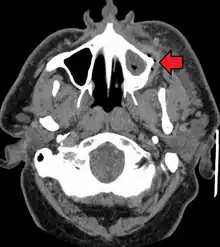

A dental infection resulting in an abscess and inflammation of the maxillary sinus

The presentation of caries is highly variable. However, the risk factors and stages of development are similar. Initially, it may appear as a small chalky area (smooth surface caries), which may eventually develop into a large cavitation. Sometimes caries may be directly visible. However other methods of detection such as X-rays are used for less visible areas of teeth and to judge the extent of destruction. Lasers for detecting caries allow detection without ionizing radiation and are now used for detection of interproximal decay (between the teeth).

Primary diagnosis involves inspection of all visible tooth surfaces using a good light source, dental mirror and explorer. Dental radiographs (X-rays) may show dental caries before it is otherwise visible, in particular caries between the teeth. Large areas of dental caries are often apparent to the naked eye, but smaller lesions can be difficult to identify. Visual and tactile inspection along with radiographs are employed frequently among dentists, in particular to diagnose pit and fissure caries.[88] Early, uncavitated caries is often diagnosed by blowing air across the suspect surface, which removes moisture and changes the optical properties of the unmineralized enamel.